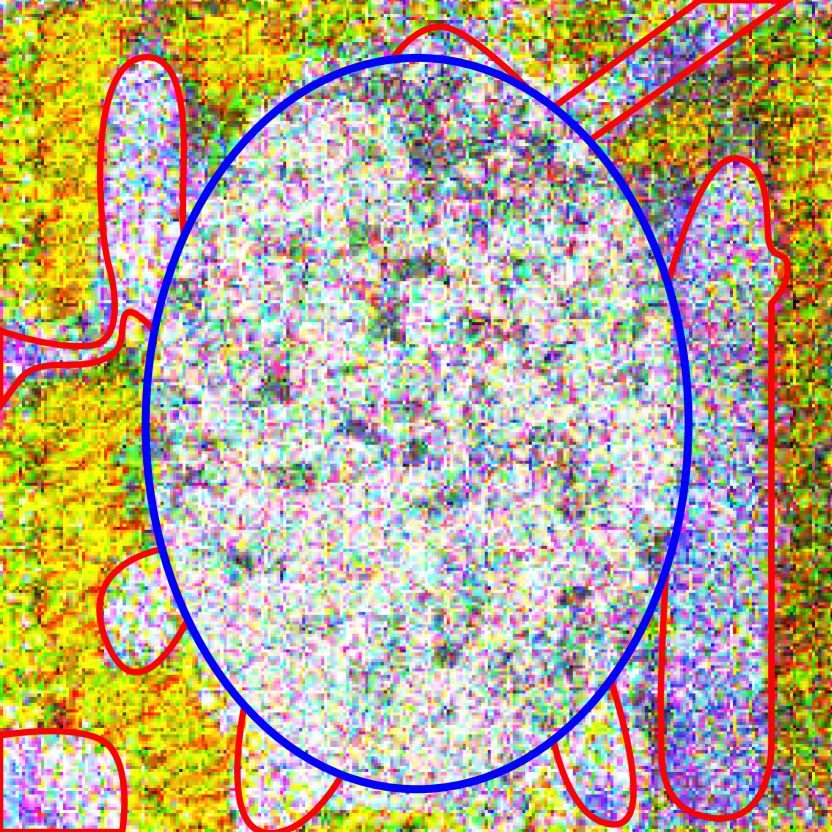

In the attacks tailored to the fundoscopic image models, perturbations introduced dark splotchy patterns to the eye area (Fig. 11). Based on diagnostic literature, these spots could be “attempts” by the attack to emulate cotton-wool spots or hemorrhages, key indicators of diabetic retinopathy [11]. Similar patterns appear in the perturbations for the chest x-ray model with attention (Fig. 9) (these spots are larger and less speckled), though these do not appear to be similar to the key indicators of pneumothoraces (air in pleural space, misplaced lung edge, less distinct lung markings, etc.) [25], it remains unclear whether the attack could be emulating these features indirectly. If so, this behavior could be responsible for medical adversarial images being so easily detected, as observed by Ma and Niu et al. (2021) [19].

While the activation maps for the dermatoscopic and fundoscopic image models were invariant to perturbation, the chest x-ray model without attention occasionally produced very different activation maps under adversarial attacks (Fig. 10). However, this was only true under successful attacks.

For all three datasets, models with attention produced activation maps that were very different from their baseline counterparts; in most cases, the regions of highest activation did not match across models. Additionally, the activation maps for the chest x-ray model with attention were highly focused, typically having a single region of significance (Fig. 10).